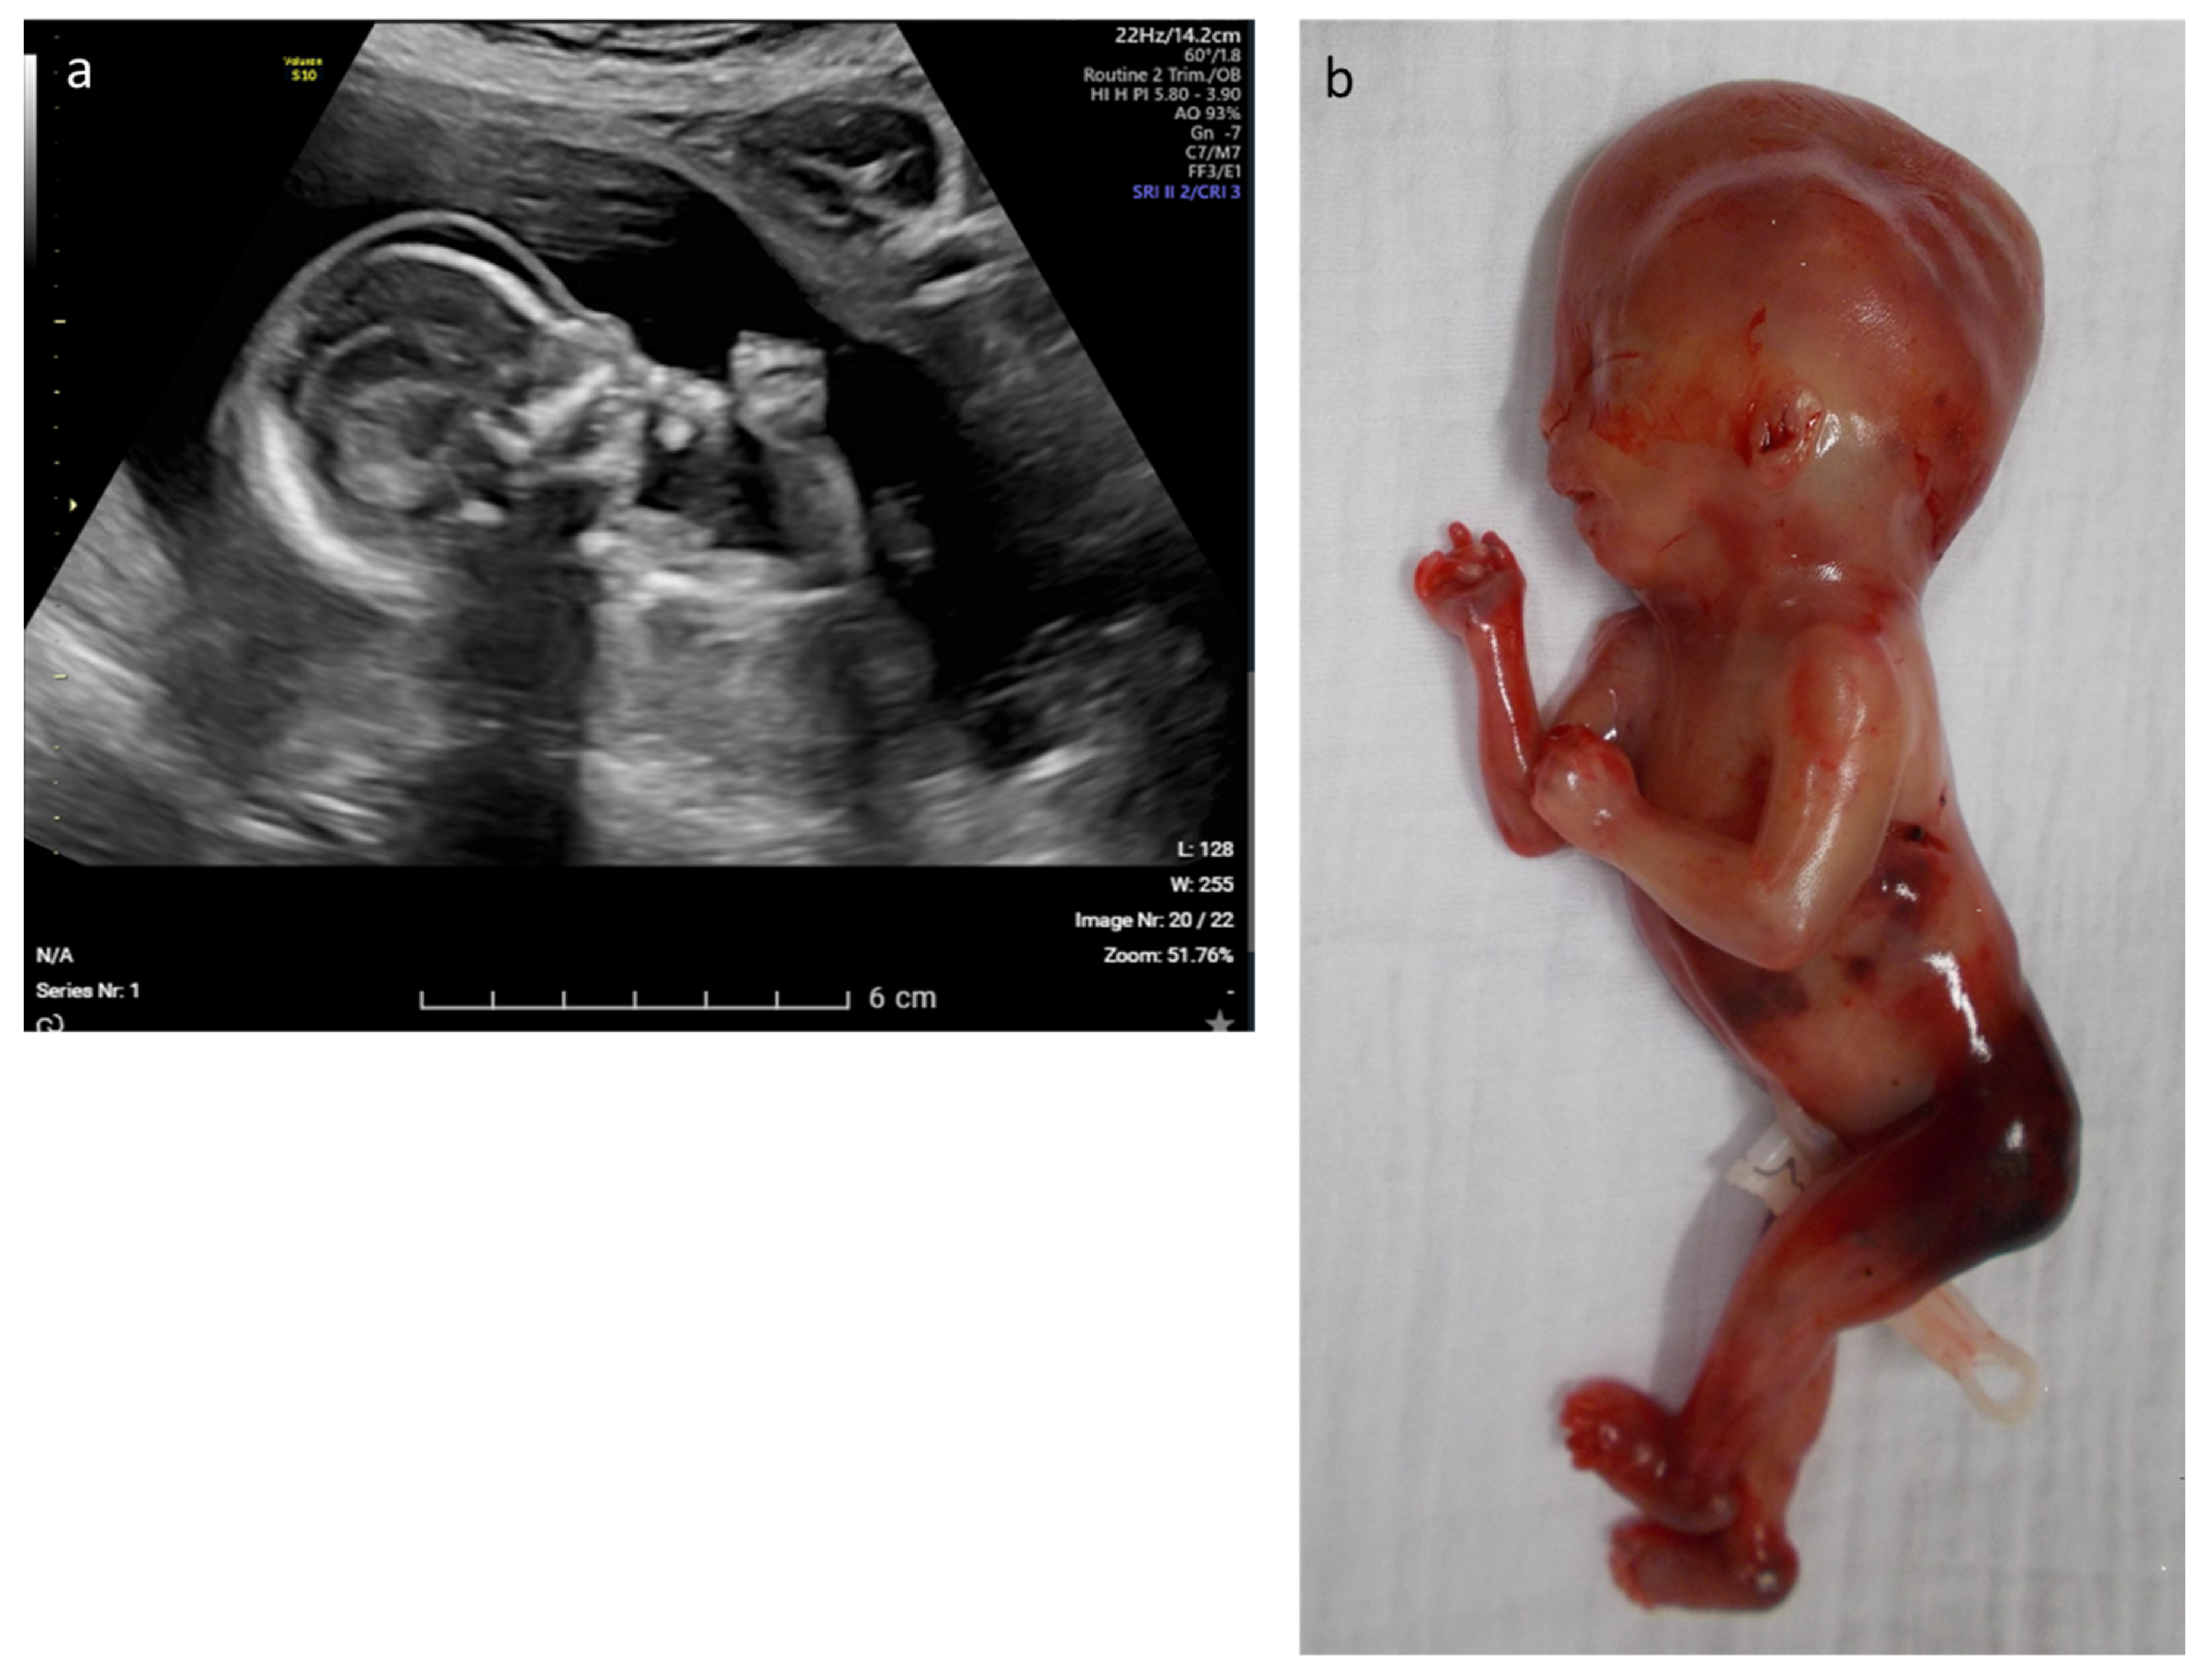

| 12 | Edema, rocker bottom foot, retrognathia, abnormal thorax and ribs, increased NT | multisystem | CHRNA1 | c.548A > G p.(Asp183Gly) | AR–hom | likely path | Multiple pterygium syndrome, lethal type (OMIM# 253290) | TOP |

| 28 | Fetal akinesia, hypotonia, rocker-bottom feet, hydrops, hydrothorax, ascites | multisystem | MUSK | c.2201G > T p.(Gly734Val) | AR–hom | likely path | Fetal akinesia deformation sequence 1 (OMIM# 208150) | TOP |